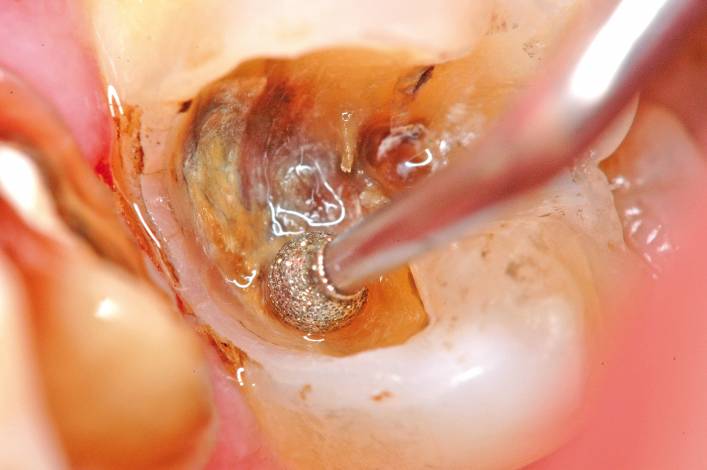

In dentistry, many daily procedures require magnification glasses or a microscope together with a mirror to observe the areas requiring treatment.

The Sopro 717 First allows you to go beyond the limits of human vision while casting off bulky accessories .

This is MacroVision.